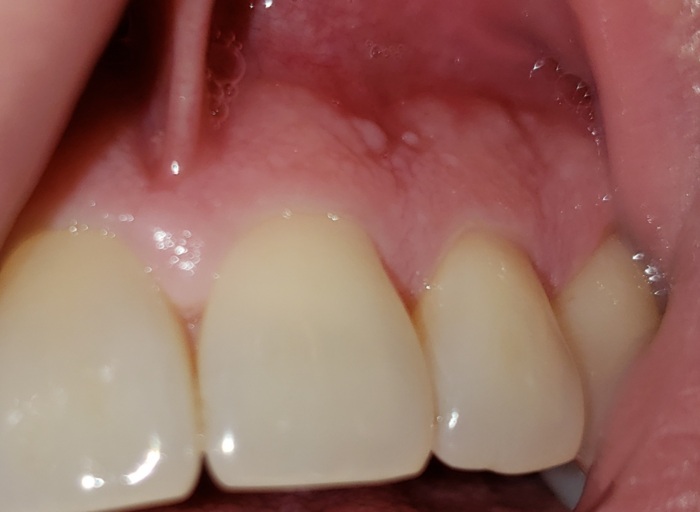

White Bumps - Harmless or Urgent?

I just noticed 3-4 days ago that I have tiny gums colored and white bumps near the roots of my teeth but in-between the teeth (primarily on the gingiva or border between gingiva and gums). They are semi hard and painless. Some appear in clusters. I...